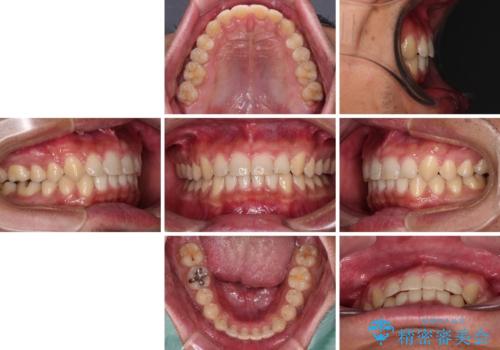

深い咬み合わせと隙間の空いた歯列をワイヤー矯正で改善

- 前歯の隙間と深い咬み合わせを改善したいとのことで来院された患者様です。

奥歯の咬み合わせは理想的な状態であったため、ワイヤー矯正でもインビザラインでも比較的容易に対応可能でした。